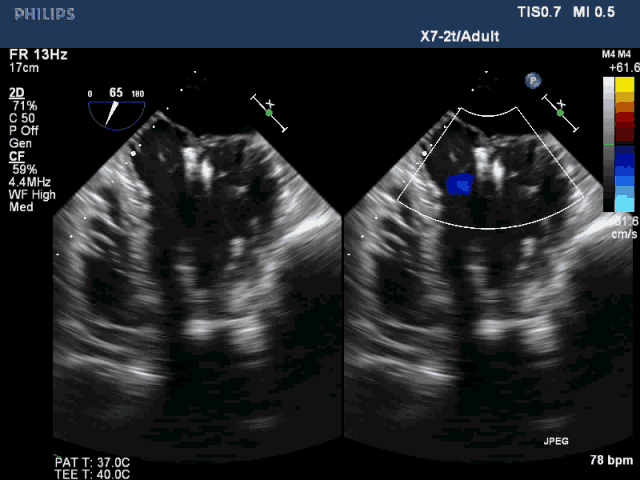

图3  植入双夹合器后反流为轻度